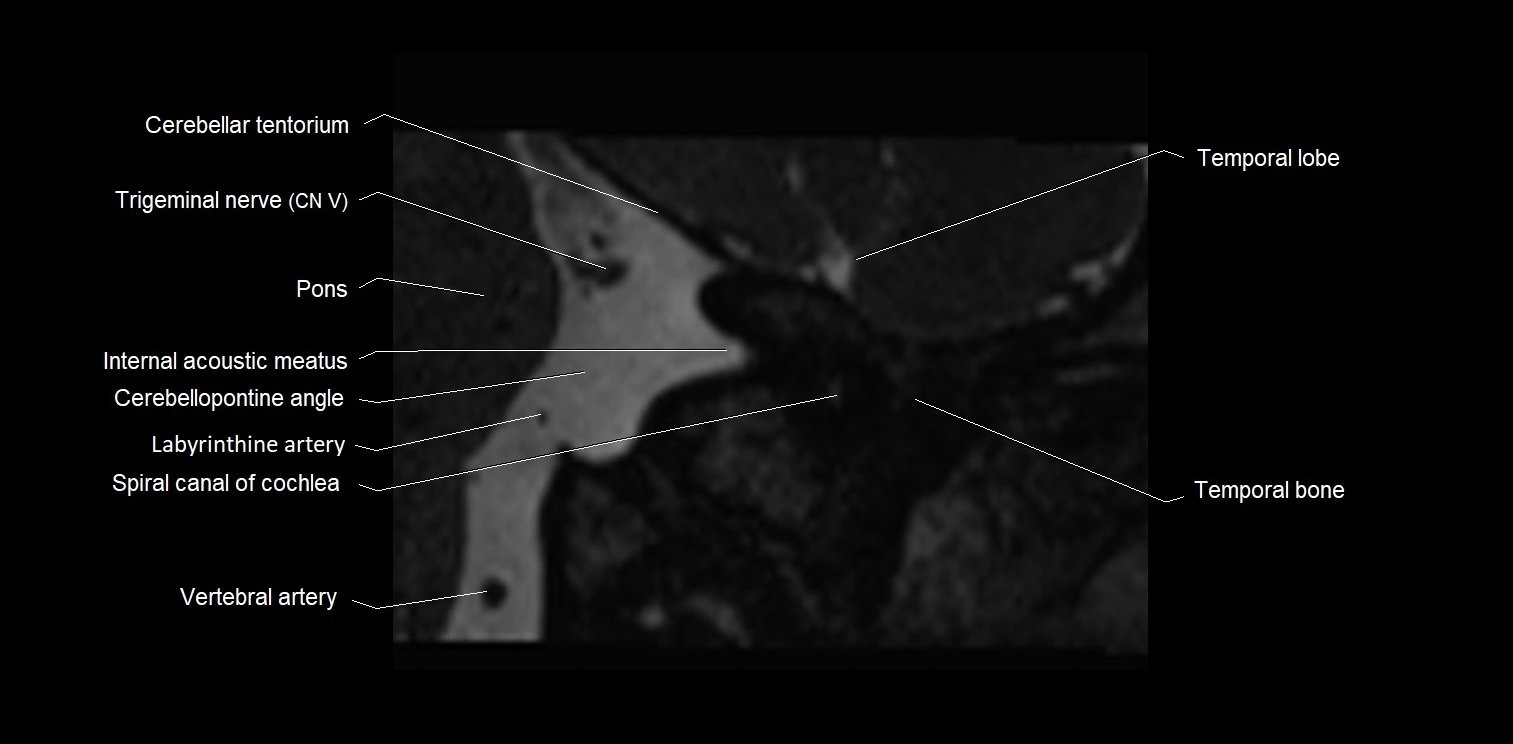

MRI images

image